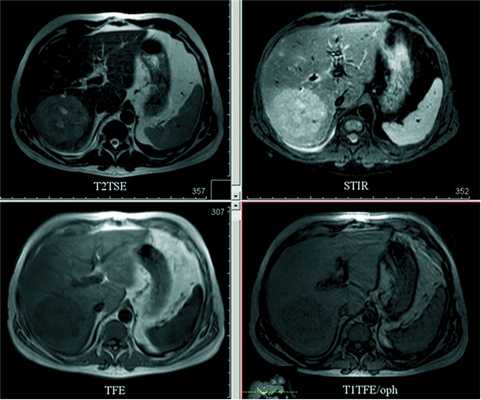

В VI-VII сегментах печени определяется объемное образование с нечеткими, волнистыми контурами, неоднородной структуры, в центре имеются неправильной формы участки с жидкостными характеристиками. Окружающая паренхима с признаками инфильтративных изменений. По верхнему контуру образования прослеживается дугообразно деформированная ветвь правой печеночной вены, по переднему контуру - смещенная ветвь средней печеночной вены (рис. 2). Рисунок 2. Магнитно-резонансная томограмма органов брюшной полости без контрастного усиления. В правой доле печени — опухолевый узел округлой формы гетерогенной структуры с неровными контурами. Наиболее отчетливо визуализируется в импульсной последовательности STIR.

При контрастном усилении отмечено накопление контрастного вещества в артериальную фазу центробежно, с наибольшей локализацией контрастного агента в центральной части (рис. 3). Рисунок 3. Магнитно-резонансная томограмма с контрастированием (нативное исследование, 15 с - артериальная фаза, 60 с - венозная фаза, более 4,5 мин - отсроченная фаза). К отсроченной фазе образование набирает контрастный препарат всем объемом, довольно гомогенно и по отношению к паренхиме печени - слабогиперинтенсивно. При этом в центральной части свободными от контрастного средства во все фазы исследования остаются жидкостные участки.